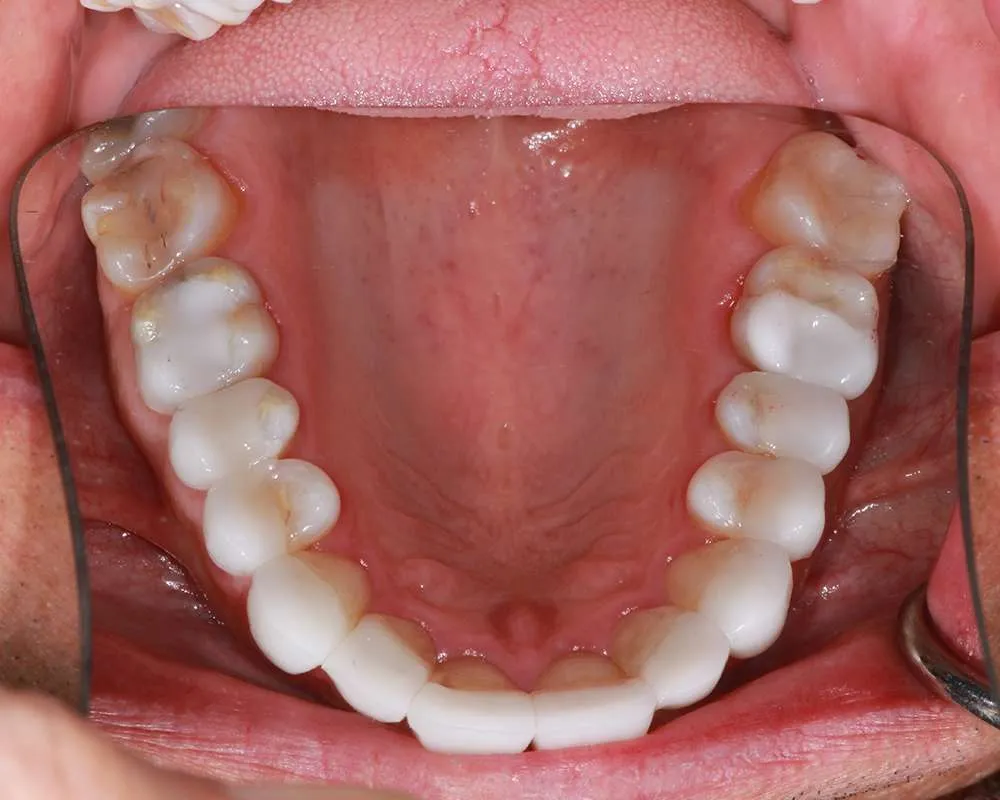

Real Stories, Real Results: Case Studies Showcasing How Our Personalized Approach Transforms Smiles and Lives

Complex Cases

Witness the Remarkable Changes We Can Achieve

Maintaining your ultra-thin veneers is straightforward and involves adhering to regular oral hygiene practices. Firstly, it’s essential to brush your teeth at least twice a day with a soft-bristled toothbrush and fluoride toothpaste. This helps to remove plaque and prevent cavities, ensuring that both your veneers and natural teeth stay healthy. Flossing daily is equally important, as it removes food particles and plaque from between your teeth and along the gumline, areas that brushing alone cannot reach.

Regular dental checkups are crucial for maintaining the health and appearance of your veneers. During these visits, we will thoroughly clean your teeth, check for any signs of potential issues, and ensure that your veneers are in excellent condition. These routine appointments help prevent problems before they start and keep your smile looking its best. Additionally, it’s wise to avoid biting into hard foods like ice, hard candy, or nuts, as these can potentially chip or damage your veneers. By following these simple care instructions, you can enjoy the longevity and aesthetic benefits of your ultra-thin veneers for many years.